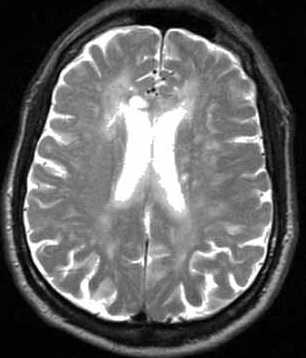

Может применяться компьютерная томография (КТ) и магнитно-резонансная томография (МРТ). С помощью КТ определяют участки пониженной плотности в центральном сером веществе среднего мозга и в части таламуса, но в большинстве случаев этот метод не выявляет очаговой патологии при острой энцефалопатии.

Наиболее эффективный метод диагностики энцефалопатии Вернике — это МРТ. Интерпретировать результаты МРТ сможет только врач.

При энцефалопатии Вернике на Т2-взвешенных МРТ головного мозга симметрично поражаются зрительные бугры, пластина четверохолмия и сосочковые тельца, иногда с участками кровоизлияний.

МРТ головного мозга позволяет найти типичные признаки энцефалита Вернике - атрофия сосочковых тел, их контрастное усиление на Т1-взвешенных МРТ с контрастированием и общую атрофию мозга. При МРТ головного мозга также описаны высокий сигнал на Т2-взвешенных изображениях от от зрительных бугров, вокруг водопровода

МРТ головного мозга. Сагиттальная Т1-взвешенная МРТ с контрастированием.. Атрофические изменения.

МРТ головного мозга. Т1-взвешенная аксиальая МРТ с контрастированием. Усиление сигнала от сосочковых тел.

МРТ головного мозга. Т2-взвешенная корональная МРТ. Высокий сигнал от зрительных бугров при энцефалопатии Вернике.